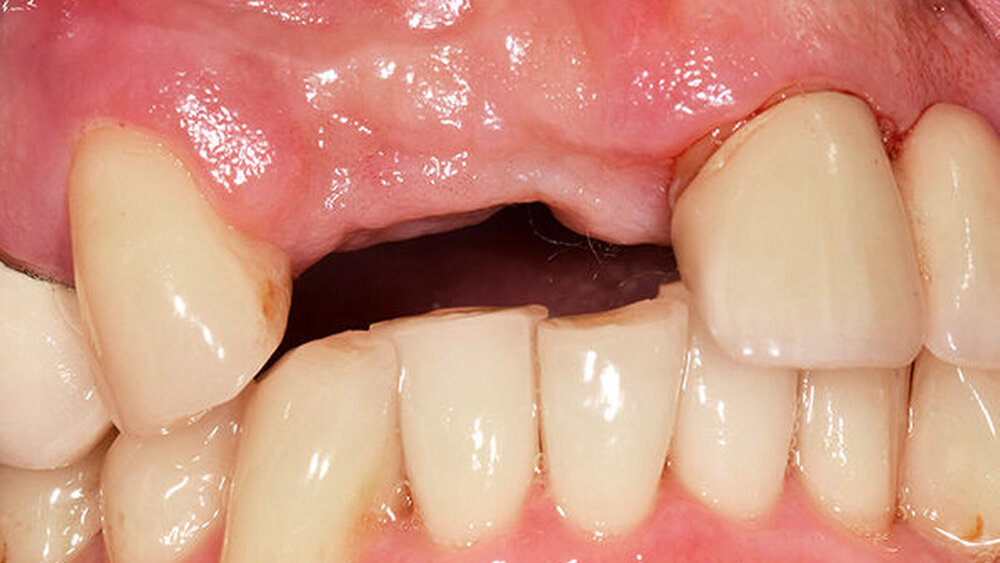

Während der komplikationslosen Heilungsphase betreute der Hauszahnarzt den Patienten. Wie geplant, erfolgte nach zwölf Wochen die Implantatfreilegung (Abb. 9) in unserer Praxis. Das Weichgewebe zeigte sich in einem blutungs- und reizfreien Zustand. Mit einer leicht palatinal orientierten crestalen Kieferkammschnittführung wurden die Implantate freigelegt, das Weichgewebe wurde nach vestibulär verdrängt (Abb. 10) und die Gingivaformer wurden aufgesetzt. Um einen quantitativen Zugewinn von keratinisiertem Gewebe zu erhalten, wurde die Naht zwischen den Implantaten nicht komplett geschlossen. Die Implantate zeigten sich klinisch und röntgenologisch sicher osseointegriert (Abb. 11).